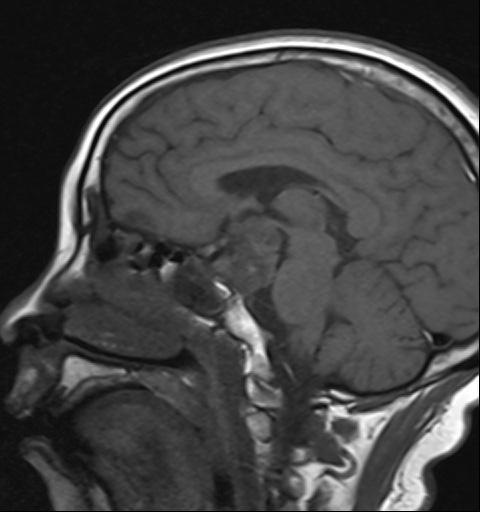

和大多数患者一样,家住郫都区的57岁的范女士也是如此。1年多前,范女士因面瘫行头部CT检查发现颅内鞍区占位。范女士当时认为占位病变不大,症状不重,又想到需要"开颅"动手术,这让她打起了退堂鼓,这一退便等了1年。直到2个月前,范女士开始出现视力下降的表现,并伴有头痛、头昏等不适,便到医院行头部MRI检查发现:鞍区占位较之前明显增大。这可将范女士愁坏了,立即和家人于6月份到郫都区人民医院神经外科就诊。本已做好开颅手术心理准备的范女士,却万万没有想到,医生既没有给自己开刀,也没有留下任何疤痕,就将颅内的肿瘤顺利切除了。

(术前检查发现肿瘤)